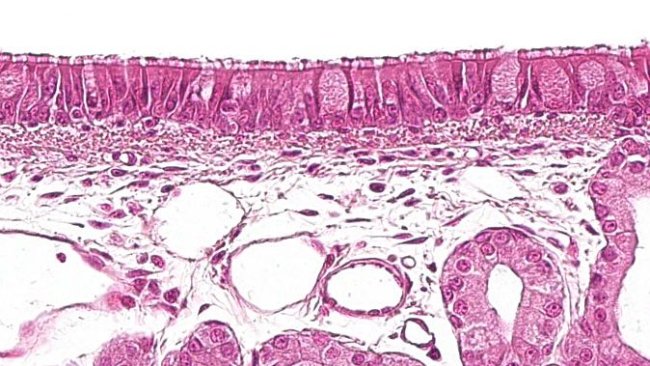

La SINS, è una sindrome ancora poco conosciuta dagli allevatori stessi, nonostante si possa evidenziare le lesioni che somigliano a necrosi della coda o infezioni podali, caratteristiche della malattia...